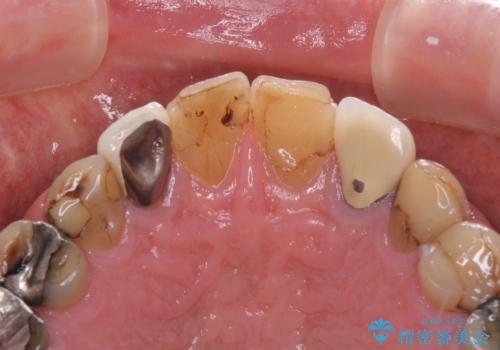

- コンポジットレジンやクラウンなど、様々な医院で治療を受けたために、統一感がなくなってしまった前歯を綺麗にしたいとのことで来院された患者様です。

黄ばんだ前歯や白すぎたクラウン、プラスチックの継ぎ接ぎなどを全てオールセラミッククラウンの統一感のある前歯に仕上げました。